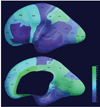

Compelling evidence indicates that psychiatric and developmental disorders are generally caused by disruptions in the functional connectivity (FC) of brain networks. Events occurring during development, and in particular during fetal life, have been implicated in the genesis of such disorders. However, the developmental timetable for the emergence of neural FC during human fetal life is unknown. We present the results of resting-state functional magnetic resonance imaging performed in 25 healthy human fetuses in the second and third trimesters of pregnancy (24 to 38 weeks of gestation). We report the presence of bilateral fetal brain FC and regional and age-related variation in FC. Significant bilateral connectivity was evident in half of the 42 areas tested, and the strength of FC between homologous cortical brain regions increased with advancing gestational age. We also observed medial to lateral gradients in fetal functional brain connectivity. These findings improve understanding of human fetal central nervous system development and provide a basis for examining the role of insults during fetal life in the subsequent development of disorders in neural FC.